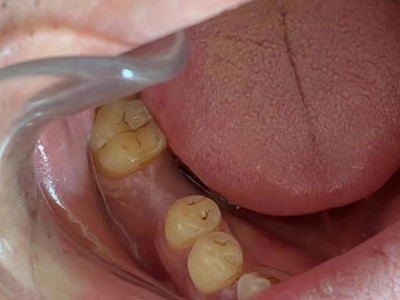

牙龈癌多源于牙间乳头及龈缘区,溃疡呈表浅、淡红,以后可出现增生。由于黏骨膜与牙槽突附着甚紧,较易早期侵犯牙槽突骨膜及骨质,进而出现牙松动,并可发生脱落。X线片可出现恶性肿瘤的破坏特征虫蚀状不规则吸收。

牙龈癌常发生继发感染,肿瘤伴以坏死组织,触之易出血。体积过大时可出现面部肿胀,浸润皮肤。